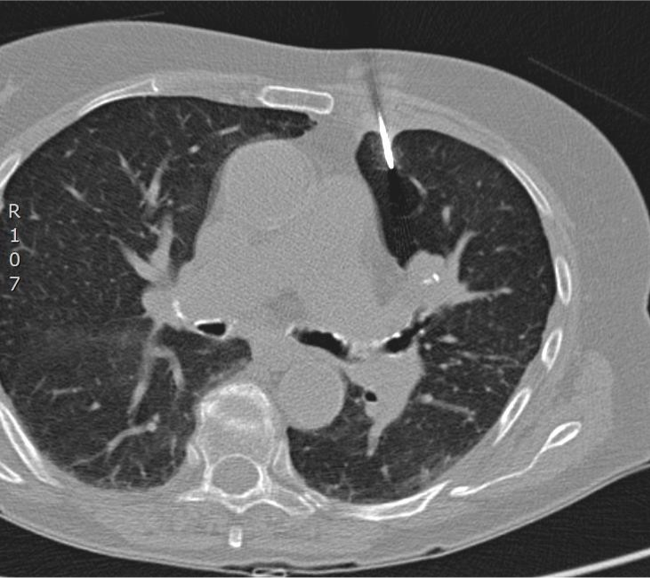

怀疑宫颈癌肺转移

病理证实:慢性感染

肺门结节

肺动脉造影证实左肺门结节(不是肺动脉)

后入路有肩胛骨,水平入路考虑病变后方为主动脉,仅经胸骨旁入路相对安全,需要避开乳内动脉,和结节后方的肺动脉和支气管。此病例活检相对风险

第一次CT扫描:观察引导针穿刺的方向和平面是否和靶病变一致(注意穿刺针的针尖不能停留在脏层胸膜表面,避免气胸)

第二次CT扫描:观察穿刺针在肺内的方向与平面是否与靶病变一致(注意每次针前进的距离是剩余针道的一半,以便随时纠正穿刺针前进的方向和水平)

引导针到病变的边缘

置换活检针

活检针进入病灶内活检,注意后方,针尖不要超过病灶的后界

拔针后显示沿针道少量肺实质出血